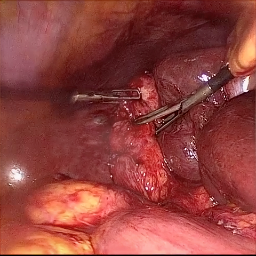

Refer to caption (a) Input Refer to caption (b) DIACMPN Refer to caption (c) Desmoke-LAP Refer to caption (d) PFAN Refer to caption (e) MITNET Refer to caption (f) Salazar Refer to caption (g) Dehamer Refer to caption (h) Ours Refer to caption (i) Target

Figure 2: Comparison of different methods on the DesmokeData dataset.

IV-C2 Qualitative Analysis

Figures 3 and 2 provide a visual comparison of the desmoking results on challenging images from the test sets. The visual results corroborate our quantitative findings. DCP not only fails to remove the dense smoke but also introduces severe color distortion. CNN-based methods like FFA-Net and MSBDN successfully remove a large portion of the smoke but tend to either leave behind a thin layer of residual haze or over-smooth the image, losing critical textural details of the tissue and surgical instruments. The Transformer-based methods, DehazeFormer and PFAN, produce significantly better results by restoring more details. However, they can sometimes struggle with non-uniform smoke distribution, resulting in regions with unnatural brightness or minor artifacts.

In stark contrast, our RGA-Net generates visually superior results that are remarkably close to the ground-truth images. It effectively removes even the densest plumes of smoke while simultaneously preserving fine-grained details, such as blood vessels, tissue textures, and reflections on surgical tools. Furthermore, the color and illumination of the restored scene appear more natural and consistent, which is a direct benefit of our model’s ability to handle both local and global features through its hybrid attention and cross-gating mechanisms. This enhanced visual clarity is crucial for improving the surgeon-robot interface in real-world clinical applications.